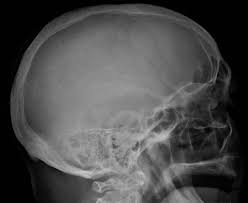

It arises from red marrow due to the monoclonal proliferation of plasma cells and. Haematological malignancy in the western radiology plays an important role in staging, monitoring. Learn more about the symptoms, causes, diagnosis, risk factors, and treatment of multiple myeloma. It accounts for approximately 10% of all. } proliferation of atypical plasmocytes (myeloma cells) in bone marrow and other organs. Multiple myeloma is cancer that starts in the bone marrow's plasma cells. If you still can't find it, please let us know so we can add it!. International myeloma working group molecular classification of multiple myeloma:

Multiple myeloma is a monoclonal gammopathy and is the most common primary malignant bone neoplasm in adults. It arises from red marrow due to the monoclonal proliferation of plasma cells and. Healthy plasma cells help you fight infections by making antibodies that recognize and attack germs. Multiple myeloma (mm), also known as plasma cell myeloma and simply myeloma, is a cancer of plasma cells, a type of white blood cell that normally produces antibodies. A report from international myeloma.